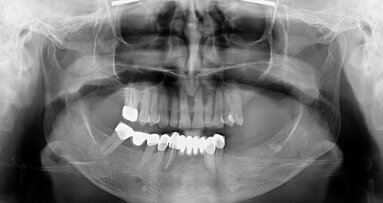

Dr Tamás Chikány graduated summa cum laude in 2009 from Semmelweis University in Budapest in Hungary and specialised in oral surgery, implantology and prosthodontics. He is co-owner and clinical director of the Intellident dental office and education centre in Budapest, where he mentors postgraduate students.

His clinical and academic expertise encompass implantology, grafting for complex hard- and soft-tissue defects, peri-implant soft-tissue management and interdisciplinary care. He serves on the board of the Hungarian Society for Dental Implantology and is an international lecturer with a leading implantology company.